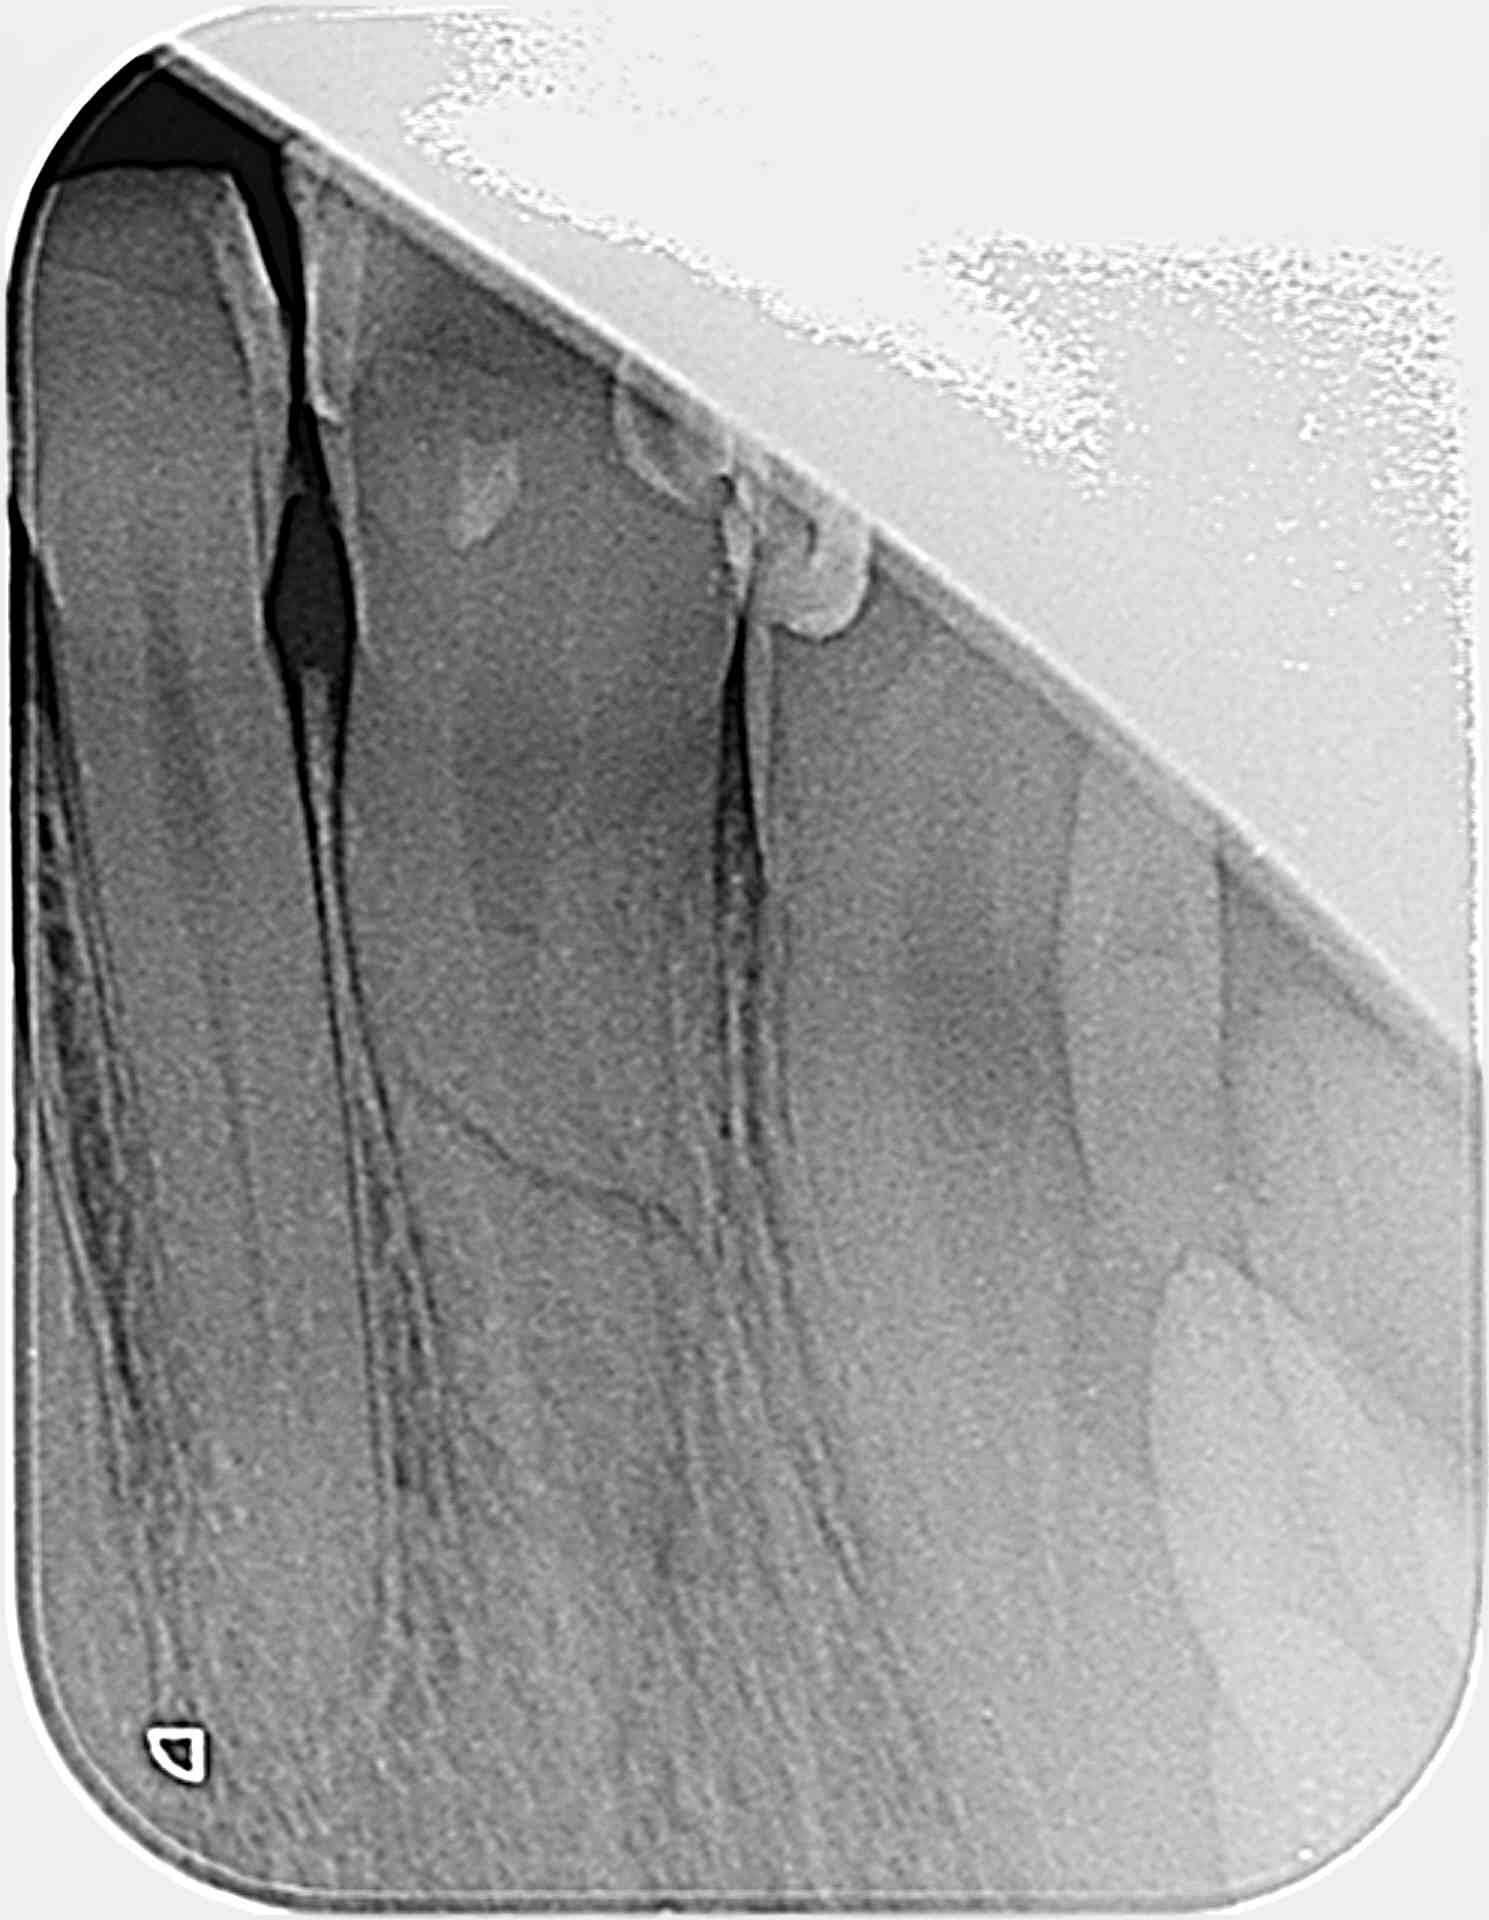

Un patient suite à un trauma s'est fracture une 11 au niveau radiculaire (milieu de racine). Le test au frois une semaine apres le choc est +. Il ya une douleur à la percussion axiale mais pas de mobilité du fragment bizarement. Que faut-il faire? depulper le fragment le plus coronaire qui va se nécroser au risque de fragiliser l'ensemble? que faire du fragment apical?

Il faut pas dépulper encore, tu verras à au moins 3 mois de suivi si test au froid négatif ou signe paro/radio, sauf si signe aigu avant évidemment. J'y toucherais pas pour l'instant.

Si pas de contact avec le milieu buccal c’est de bon pronostic. Une cicatrisation entre les deux fragments va se mettre en place au pire tu feras l’endo du fragment coronaire seul, y’a de forte chance que le fragment apical reste vital. La sensibilité à la percussion est pas étonnante à ce stade à mon avis c’est pas un critère de pulpectomie...